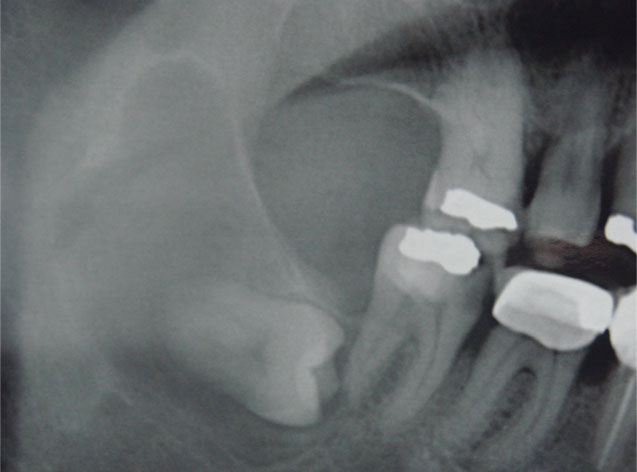

Aunque su estirpe anatomopatológica sea benigna, son quistes que en algunos pacientes provocan grandes destrucciones maxilares, porque crecen de forma asintomática durante años.

Su cirugía es sencilla y está basada en la extracción del quiste con criterios conservadores, y en la reconstrucción del defecto creado por la limpieza quirúrgica.